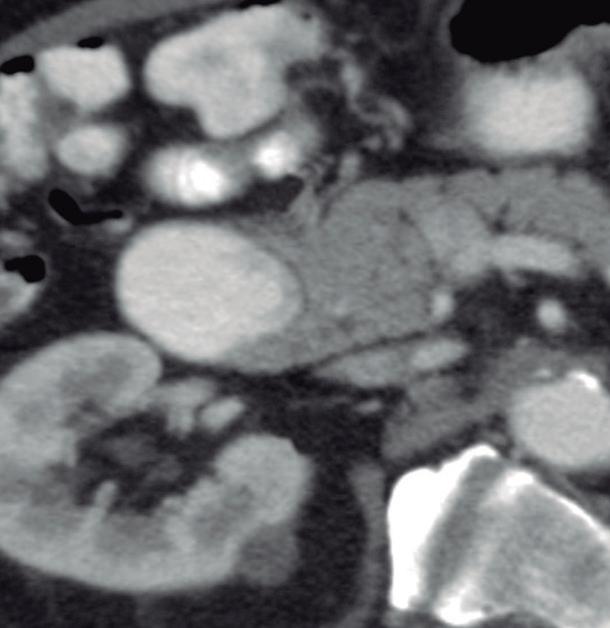

Consiste en una anomalía de la migración del brote pancreático ventral, el cual no rota o lo hace de manera incompleta, resultando en la presencia de tejido glandular pancreático a la derecha del duodeno, rodeando a su 2° porción (Figura 8). Han sido descriptos dos subtipos: el extramural, donde el conducto de Wirsung rodea al duodeno uniéndose al conducto pancreático principal; y el intramural, donde el tejido pancreático se entremezcla con la pared duodenal y sus secreciones drenan directamente a la luz a través de conductos muy pequeños.16

En las imágenes encontramos parénquima pancreático rodeando a la 2° porción duodenal, habitualmente en toda su circunferencia y en ocasiones de manera incompleta. En la colangio-RM es posible visualizar al conducto pancreático a la derecha del duodeno, con un recorrido que se dirige a la ubicación de la papila mayor (Figura 9).17

A) Resonancia magnética secuencia T1 con gadolinio, plano axial. Las flechas señalan el parénquima del páncreas prolongado hacia la derecha “abrazando” a la 2° porción duodenal (cabeza de flecha). B) Resonancia magnética, secuencia T1 con gadolinio, plano axial, corte más caudal al previo. Las flechas nos muestran al páncreas rodeando de manera completa a la 2° porción del duodeno. C) Resonancia magnética, secuencia T2, plano coronal. La flecha señala presencia de parénquima glandular y conducto pancreático a la derecha del duodeno (cabezas de flecha). D) Resonancia magnética, secuencia T2, plano coronal, corte posterior al previo. El páncreas anular y su conducto de drenaje rodean en forma completa al duodeno (cabezas de flecha). E) Colangio-RM. El conducto del páncreas ventral (flechas) hace un giro, rodea al duodeno (cabeza de flecha) y se une al conducto pancreático principal para drenar en la papila mayor. F) Colangio-RM. La imagen magnificada muestra con mayor detalle el recorrido del conducto de Wirsung en el contexto de un páncreas anular.